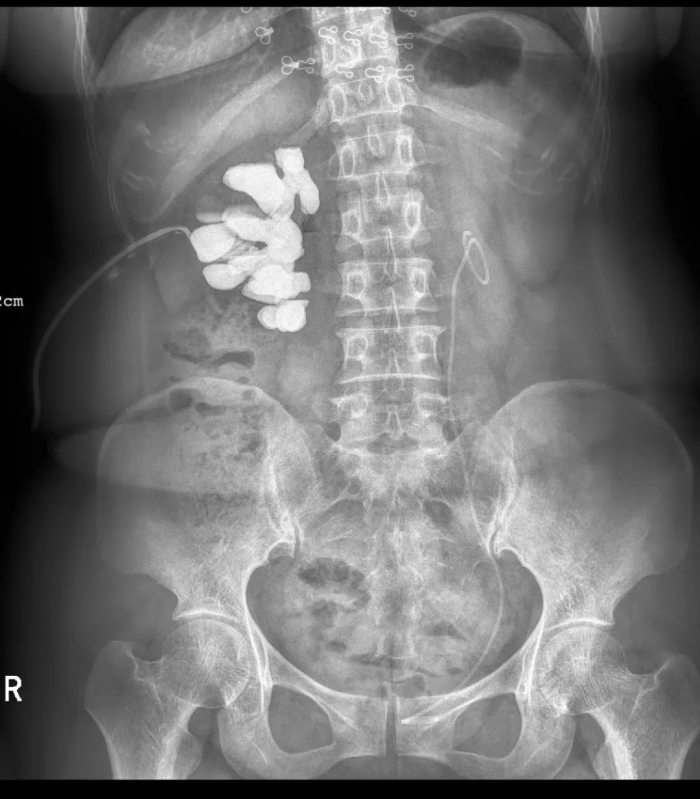

9月20日,在湘雅医院泌尿外科祖雄兵主任的指导下,贵阳市一医泌尿外科肖峰团队,采用双镜联合方式,成功为一位钬激光结石术后、肾内型肾盂狭窄、功能性孤肾女性患者置入了温控记忆合金永久支架(梅莫凯斯支架),彻底解决了困扰患者多年的输尿管狭窄问题。这是我省首例输尿管狭窄“温控记忆合金支架”置入手术。目前,患者状态良好,手术取得圆满成功!